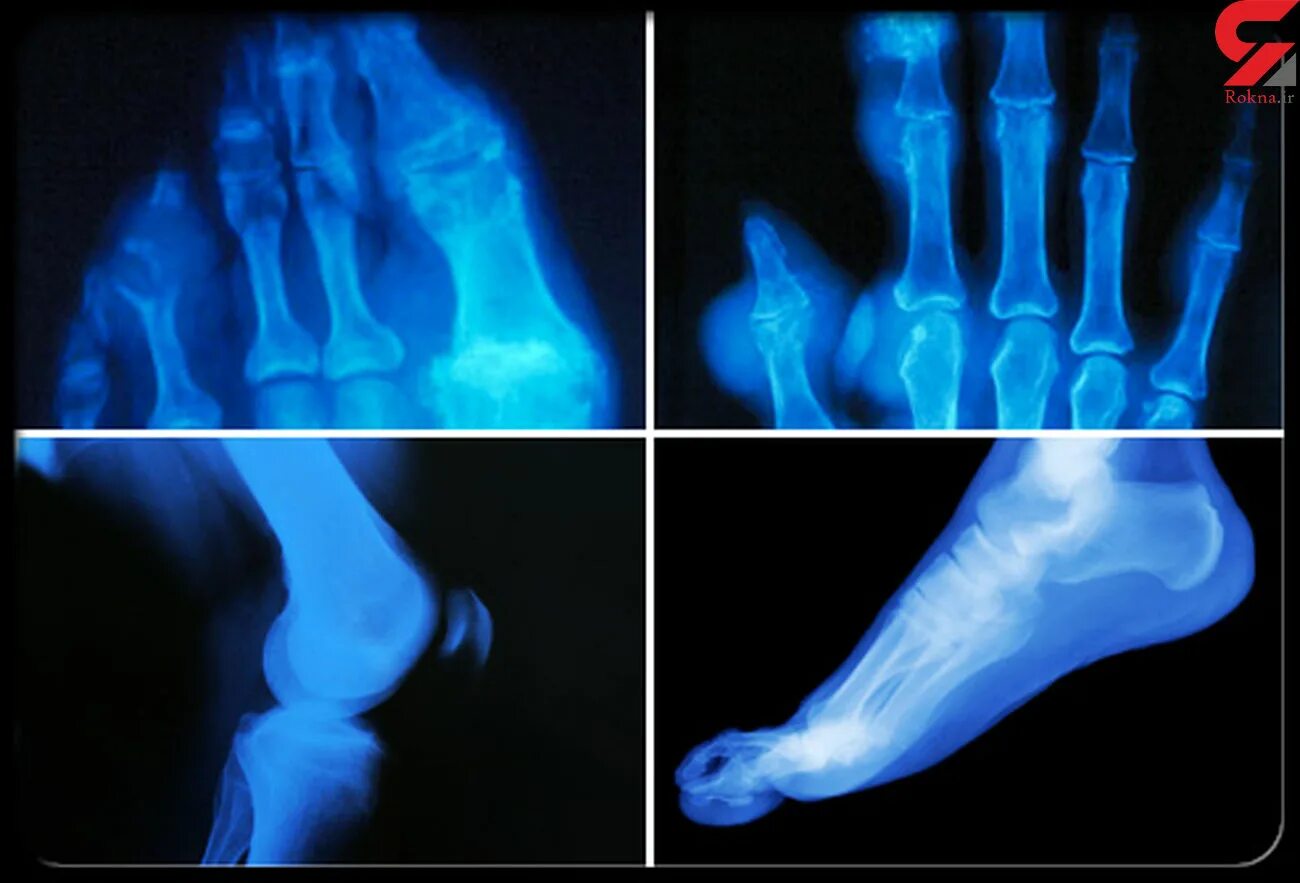

Подагра суставов стопы